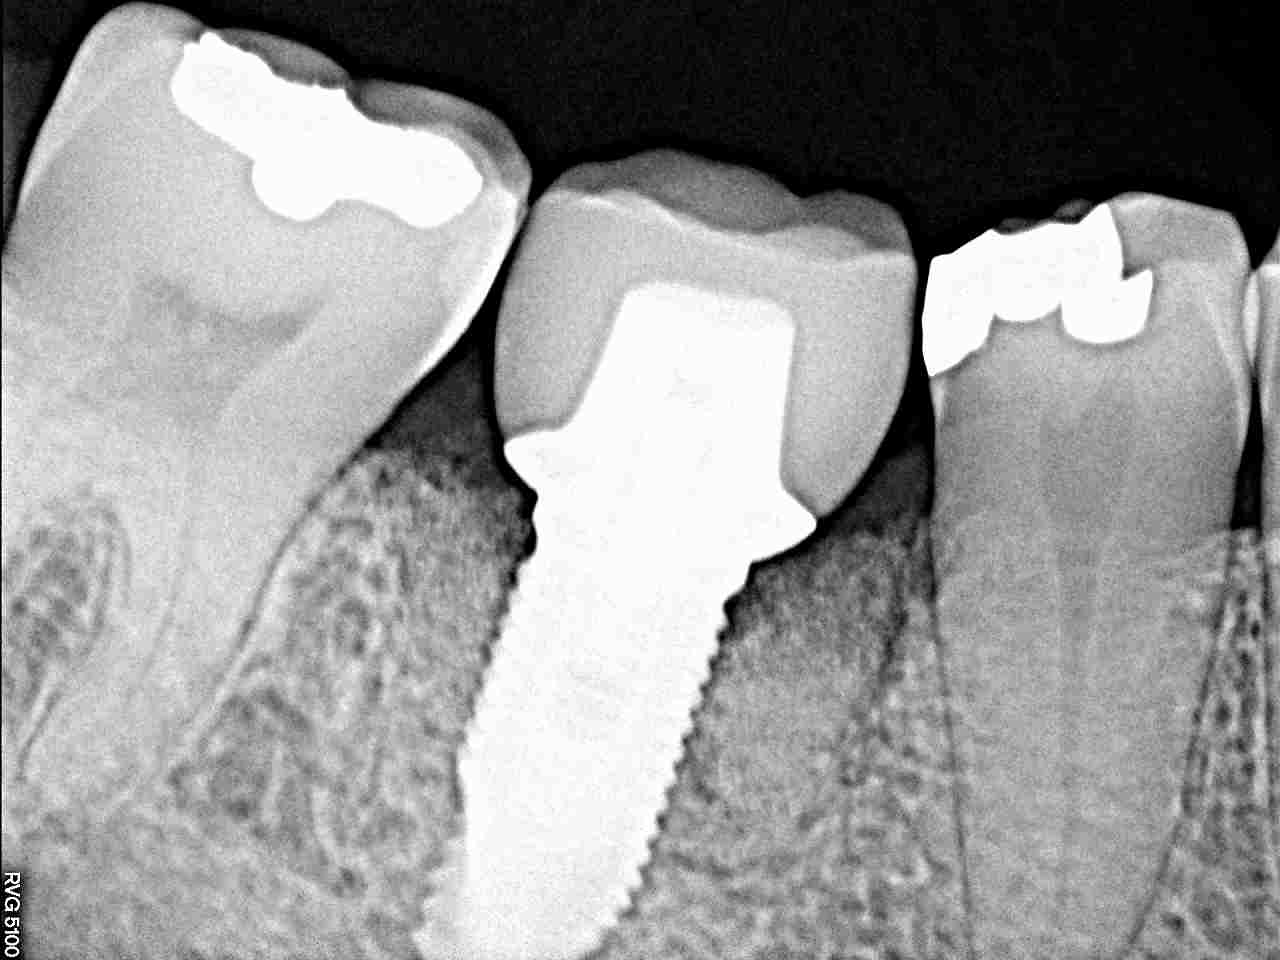

口蓋側寄りにしっかりと5㎜の11,5㎜というインプラントを埋入

しています

デンタルレントゲンにて

抜歯即時とは言え治療期間も抜歯して3ケ月以内

しっかりとしたインプラントが入ったと思います